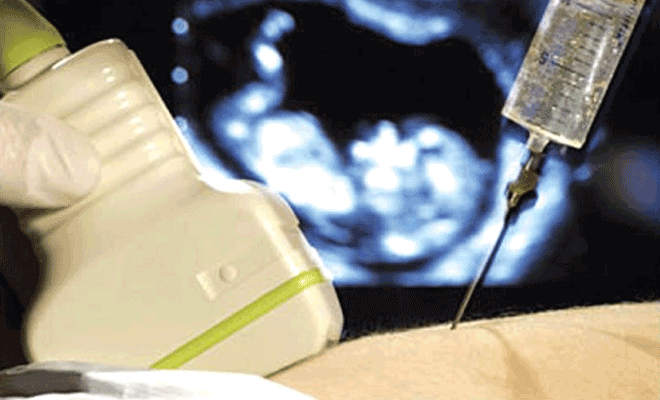

- سپس تحت سونوگرافی، پزشک سوزنی نازک و بلند را وارد دیواره شکم و کیسه آب (علائم پارگی کیسه آب جنین) اطراف جنین می کند. پزشک مقداری مایع آمونیاک خارج می کند.

اولا، پزشک از سونوگرافی برای تعیین محل دقیق نوزاد در رحم استفاده می کند. شما بر روی یک میز معاینه دراز می کشید. پزشک یک ژل مخصوص بر روی شکم شما اعمال می کند و سپس از یک دستگاه کوچک که به عنوان یک مبدل اولتراسوند شناخته می شود استفاده می کند تا موقعیت جنین را روی مانیتور نشان دهد.

سپس پزشک شکم را با یک ماده ضد عفونی کننده تمیز می کند. به طور کلی، بیهوشی استفاده نمی شود. اکثر زنان در طی این عمل فقط ناراحتی خفیفی را گزارش می دهند. با هدایت سونوگرافی پزشک یک سوزن نازک و توخالی را از طریق دیواره شکم و رحم وارد می کند. مقدار کمی مایع آمنیوتیک با یک سرنگ برداشته می شود و سوزن خارج می شود. مقدار مایع آمنیوتیک خارج شده بستگی به تعداد هفته های حاملگی دارد. هنگامی که سوزن وارد پوست شما می شود احساس سوزش می کنید و وقتی که سوزن وارد رحم می شود، احساس گرفتگی می کنید.